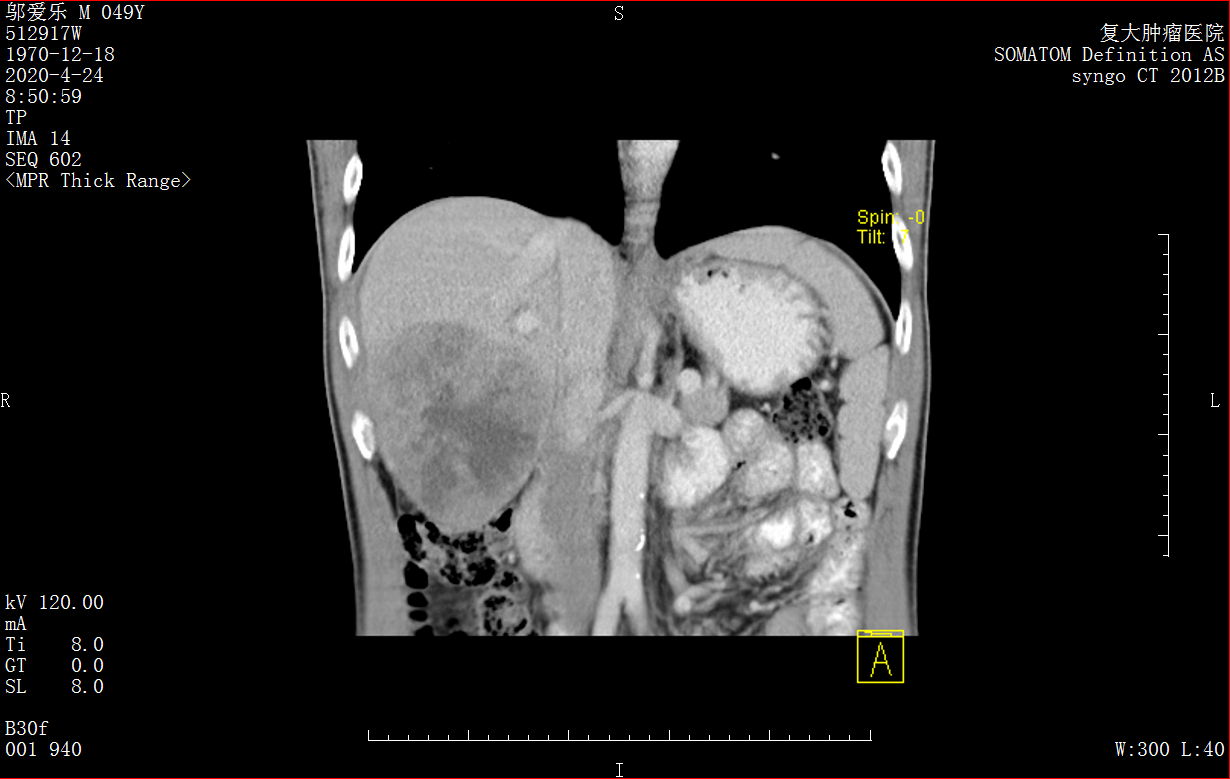

Снимок КТ печени до операции